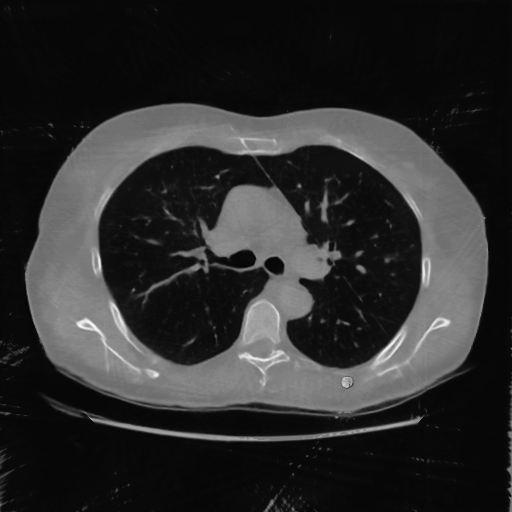

IV-F Real CT Reconstruction

To further verify the effectiveness of the RBP-DIP framework, real CT data from the Finnish Inverse Problem Society [49, 50] was used to validate our algorithm. The few-view and limited-angle reconstruction results are shown in Figure 12. Due to the lack of available training sets, pre-trained models were not included in the experiments. Different from the previous experiment, data from Finnish Inverse Problem Society is highly noisy. However, it is still evident that the RBP-DIP outperforms all other algorithms in all experiments, even under high noise and highly ill-posed conditions.

SNR/SSIM

10.94dB/0.41

13.60dB/0.40

16.25dB/0.53

10.79dB/0.45

13.91dB/0.47

16.49dB/0.57

9.74dB/0.30

12.22dB/0.26

14.46dB/0.42

(a) Reference

8.41dB/0.34

(b) ASD-POCS

12.77dB/0.31

(c) DIP

14.59dB/0.45

(d) RBP-DIP